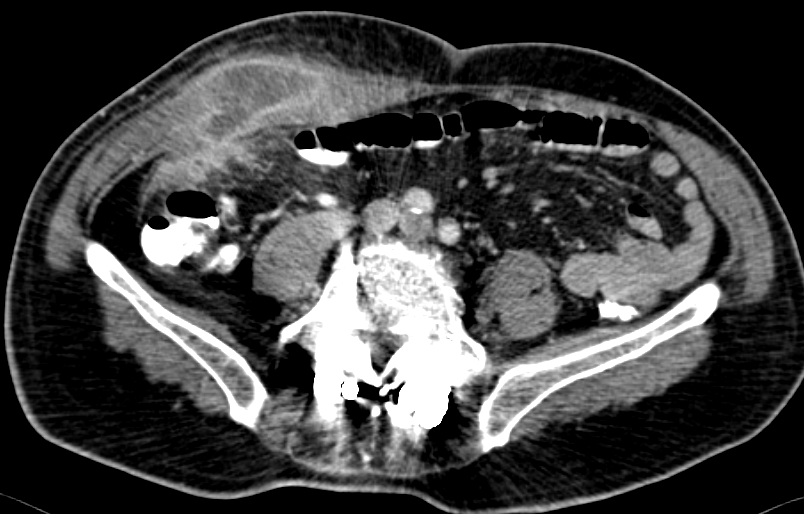

CT scan κοιλίας. Παρουσία ασβεστώσεων, κυστικο-συμπαγών περιοχών και λιπώδους ιστού, ενδεικτικά τερατώματος δεξιάς πλευράς (Ευγενική παραχώρηση Dr. V. Penopoulos)